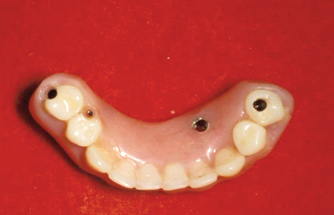

As an alternative to the relatively expensive traditional hybrid restoration that the senior population may perceive as unattainable at their age, an immediate-load all-resin provisional may often be a reasonable option as an entry-level prosthesis. This can serve for extended periods or indefinitely, and when made with a sufficient volume of resin and opposing a light occlusion such as a maxillary denture, it can offer the benefit of fixed retention at a significant reduction in expense (Figure 15 and Figure 16). Technology involving a guided approach for placing three implants universally in the same sites with pre-manufactured, one-size-fits-all bar components in the mandible can now allow placement of a final restoration in one day, again at a significantly reduced cost (Figure 17 and Figure 18).24-26 Both of these fixed options—the resin long-term provisional and the three-implant bridge—are economically comparable to the most commonly considered implant prosthesis for elderly patients, the two-implant overdenture. In contrast to the latter, however, both fixed restorations offer significant advantages in bite force, bone preservation, maintenance, and patient satisfaction that are simply unachievable with the removable implant overdenture prosthesis.27-31

Fig 15. This all-resin interim restoration, which served as a fixed long-term provisional for more than 5 years, is an example of an entry-level option that offers the physiologic benefits of a long-term fixed restoration but with an economic equivalence to a mandibular two-implant overdenture.

Figure 15

Fig 16. This all-resin interim restoration, which served as a fixed long-term provisional for more than 5 years, is an example of an entry-level option that offers the physiologic benefits of a long-term fixed restoration but with an economic equivalence to a mandibular two-implant overdenture.

Figure 16

Fig 17. A three-implant fixed bridge may be an immediate-load alternative for a fixed restoration as opposed to a two-implant overdenture. In addition to significant cost reduction due to pre-manufactured components, the final long-term restoration is delivered on the day of surgery.

Figure 17

Fig 18. A three-implant fixed bridge may be an immediate-load alternative for a fixed restoration as opposed to a two-implant overdenture. In addition to significant cost reduction due to pre-manufactured components, the final long-term restoration is delivered on the day of surgery.

Figure 18